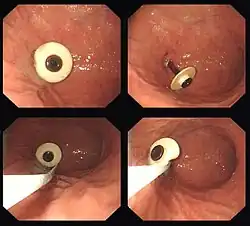

- Button-Sonde: Die perkutane Austauschsonde hat innen einen Ballon oder eine andere Vorrichtung, um einen Wechsel durchzuführen, und außen keinen Schlauch, sondern nur einen Knopf mit einem Deckel, welche unauffällig unter der Kleidung getragen werden kann. Zum Sondieren wird ein Verbindungsstück angeschlossen. Meist erfolgt der Einsatz eines Buttons, nachdem bereits eine PEG angelegt wurde. In selteneren Fällen wird aber auch ein Button chirurgisch angelegt.